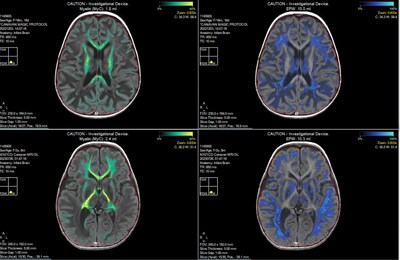

- Significant increases in brain myelin volume were demonstrated using Synthetic MRI (SyMRI), indicating new myelination.